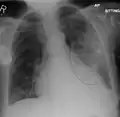

A chest X-ray showing a very prominent wedge-shape bacterial pneumonia in the right lung

The discovery of x-rays made it possible to determine the anatomic type of pneumonia without direct examination of the lungs at autopsy and led to the development of a radiological classification. Early investigators distinguished between typical lobar pneumonia and atypical (e.g. Chlamydophila) or viral pneumonia using the location, distribution, and appearance of the opacities they saw on chest x-rays. Certain x-ray findings can be used to help predict the course of illness, although it is not possible to clearly determine the microbiologic cause of a pneumonia with x-rays alone.